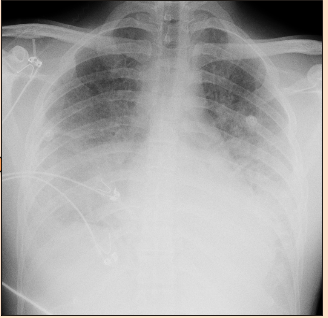

La analítica sanguínea muestra unos lactatos de 3,5 mmol/l, una leucocitosis de 22000, una creatinina de 1,37 mg/dL y trombocitopenia (125x109L). Se recogen hemocultivos. Se solicita una radiografía portátil👇

El paciente empieza a empeorar respiratoriamente. Cada vez las necesidades de oxígeno son mayores.